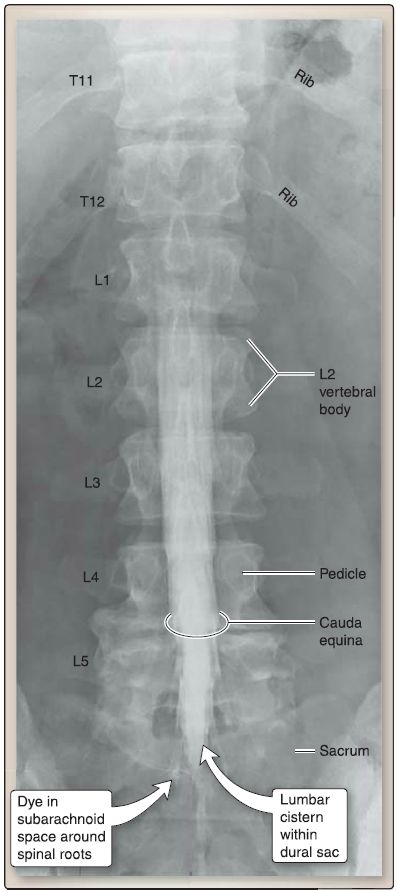

Housed and protected within the vertebral column, the spinal cord spans from the foramen magnum to approximately the L2 vertebral level in the adult (Fig. 1). As part of the central nervous system (CNS), the spinal cord serves as a reflex center and conducts motor and sensory signals between the brain and the body. The vertebral column also contains vasculature, adipose, and meningeal layers, which supply and protect the spinal cord, respectively. The spinal cord is cylindrical in shape with enlargements in the cervical and lumbar regions to accommodate for upper and lower limb innervation, respectively. Distally, the spinal cord tapers and ends at L2 as the conus medullaris. Multiple spinal nerve rootlets emerge from the distal spinal cord and conus medullaris to exit the vertebral column. They are collectively referred to as the cauda equina .

2. Arachnoid mater: Deep to the dura mater is the arachnoid mater, a delicate, web-like layer that creates a subarachnoid space filled with cerebrospinal fluid (CSF). CSF bathes and protects the spinal cord and nerve roots within the vertebral canal. The subarachnoid space also contains arterial and venous branches that nourish the spinal cord. Under normal conditions, the arachnoid and dura are closely associated, obliterating the subdural space between these two layers. However, bleeding can occur into this space, forming a subdural hematoma. A widened subarachnoid space exists below the level of the conus medullaris between vertebral levels L2-S2. This space, referred to as the lumbar cistern, lies within the dural sac and contains CSF and the cauda equina.

Figure 5 : Lumbosacral myelography.